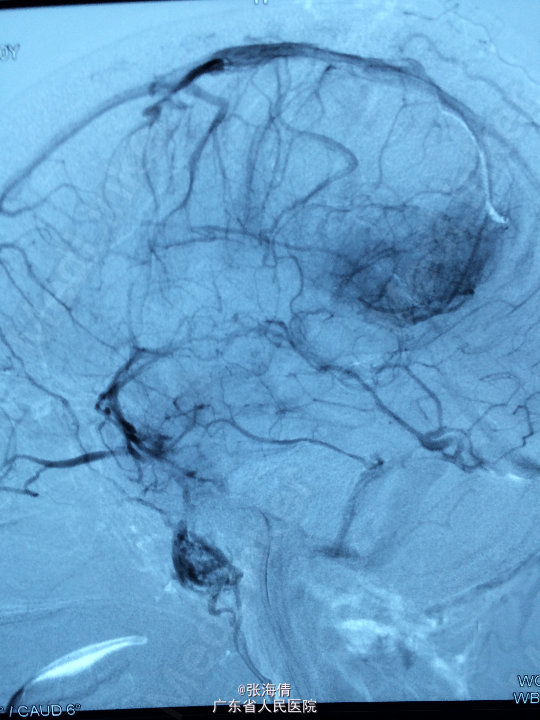

主诉:头晕、恶心6h 病史:患者男,22岁,2年来头晕、恶心症状多次出现,发作频率无明显规律,每次约2 min,无其他不适。6小时前上述症状加重,伴呕吐,呕吐物为胃内容物,外院CT平扫:示右侧颞顶叶见结节状稍高密度影,外院MR提示:平扫示右颞顶叶可见结节状稍长T1混杂T2信号影,大小约2.5 cm×2.1 cm×2.6 cm,边界较清晰,周围见长T1长T2水肿信号,SWI序列病变内未见明显低信号,DWI示信号稍高,增强扫描明显均匀强化,可见分叶,右侧脑室后角轻度受压

查体:全身未触及明显肿大淋巴结。脑膜刺激征:颈项强直,Kernig’S征阳性。 辅助检查:外院CT平扫:示右侧颞顶叶见结节状稍高密度影,外院MR提示:平扫示右颞顶叶可见结节状稍长T1混杂T2信号影,大小约2.5 cm×2.1 cm×2.6 cm,边界较清晰,周围见长T1长T2水肿信号,SWI序列病变内未见明显低信号,DWI示信号稍高,增强扫描明显均匀强化,可见分叶,右侧脑室后角轻度受压

诊断:脑膜瘤 处理:先予DSA以明确肿瘤供血情况,术中脑膜瘤供血丰富,用PVA颗粒超选到供血动脉将其闭塞。后再择期在气管全麻下行脑膜瘤切除术。

术后病理提示:脑膜瘤,WHO I级,瘤组织浸润脑组织。免疫组化:Ki一67(<1%)(+),CK(一),GFAP(一),Vimentin(+),EMA(+),P53(一),ER(一),PR(一)。 讨论:脑膜瘤首选方法为手术切除,手术切除脑膜瘤是最有效的治疗手段,但是由于其供血经常较为丰富,故可先行介入栓塞供血动脉后再行切除,这样可以降低手术风险和手术难度,改善患者手术预后。